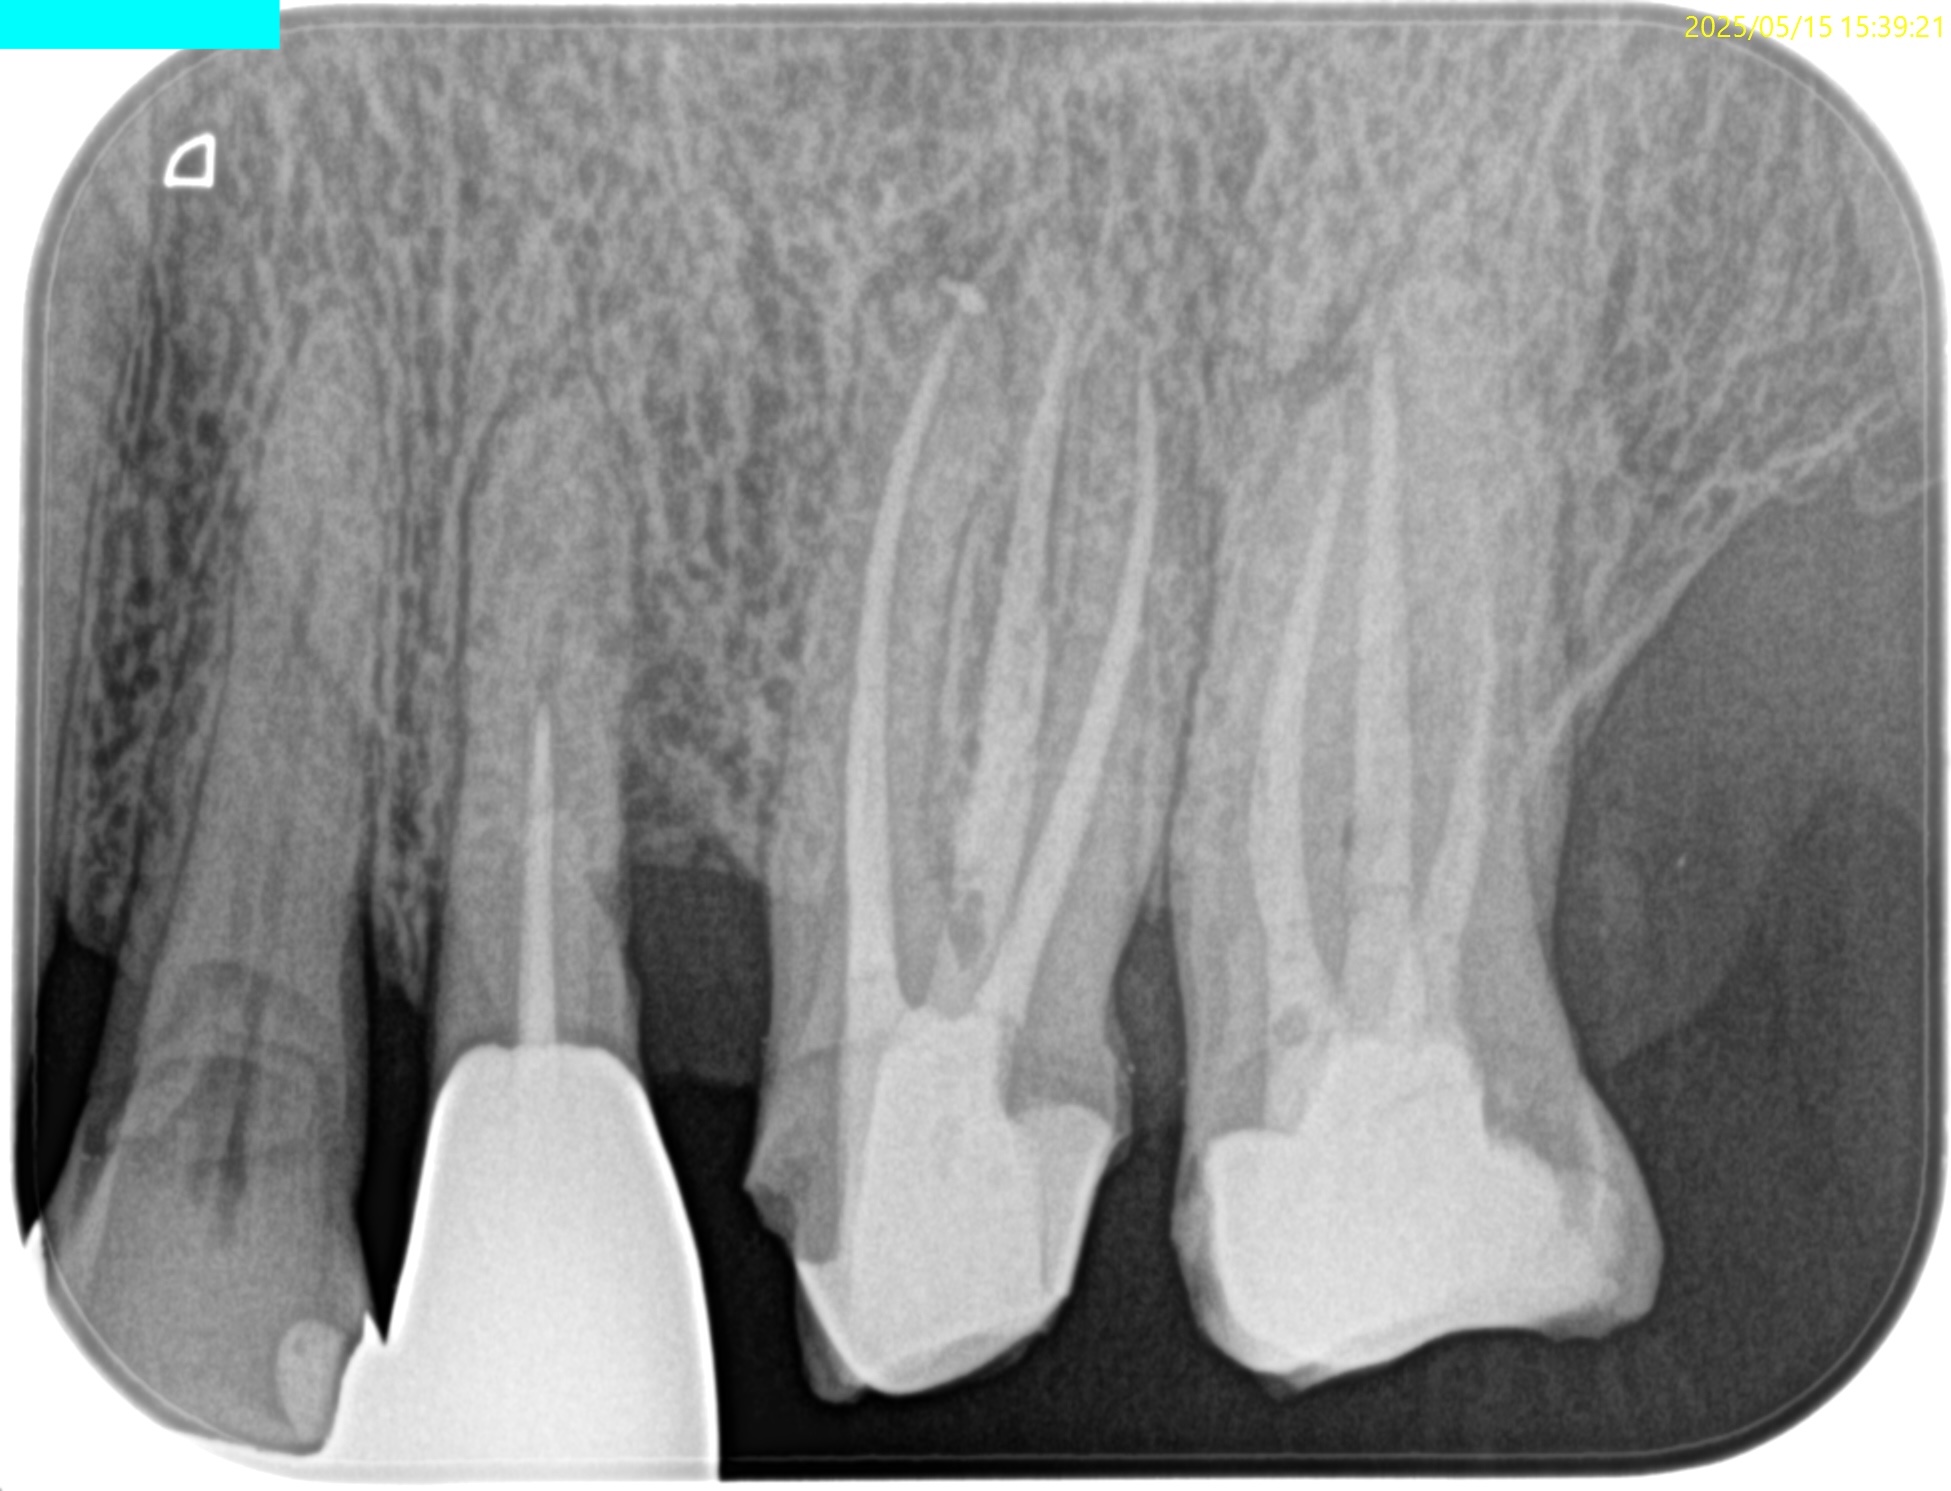

PA(2025.5.15)

根尖病変があるのはMBのみだ。ここが主訴の病因だろう。

MB2はMB1の近傍にあることがわかる。